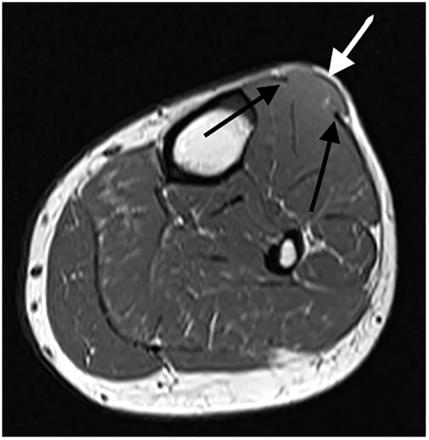

胫骨前肌肌疝

图片尺寸1334x1002